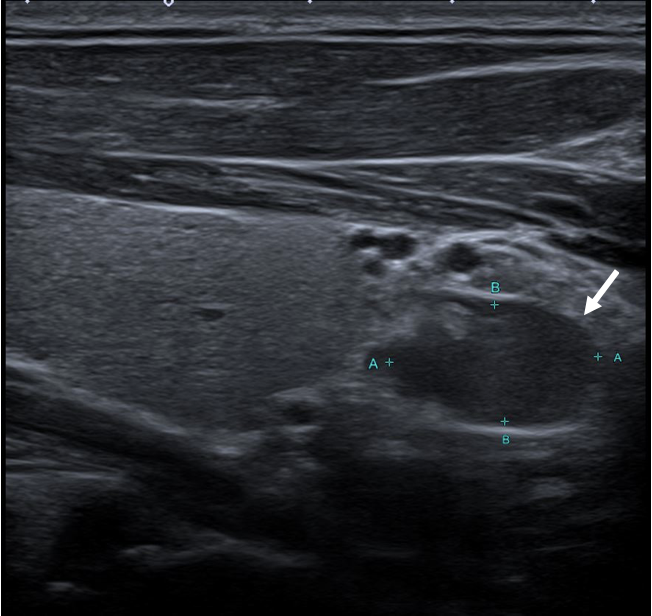

An ultrasound examination of the chest performed using a Toshiba Aplio 500 high-frequency probe showed an acute linear fracture through the anterior cortex of the sternum just below the level of the sternomanubrial joint (FIGURE 1). The subjacent third costal cartilage was unremarkable. A bone densitometry DEXA scan showed osteoporosis of the L2-L4 vertebral bodies with both T-score and Z-scores measuring -2.9 (FIGURE 2). Bone density of the bilateral femora was normal (T score -0.9). Further imaging of the neck was arranged to investigate the cause of the inappropriate parathyroid hormone levels. An ultrasound of the neck revealed a well-defined, hypoechoic nodule located just inferior to the lower pole of the left lobe of the thyroid gland measuring 14x8x5mm (FIGURE 3). The patient then underwent a SPECT-CT of the neck and chest to ensure co-localisation on two imaging modalities. 739 MBq of technetium 99m was injected and acquisitions were obtained at 10min, 90mins and 180mins following tracer injection. Analysis of the SPECT data demonstrated a well-defined area of retained activity situated in the lower pole of the left lobe of the thyroid which correlated well with the findings of the ultrasound scan (FIGURE 4). The overall appearances were in keeping with a parathyroid adenoma situated in the lower pole of the left lobe of the thyroid. The CT component of the study also showed a further view of the fracture (FIGURE 5).